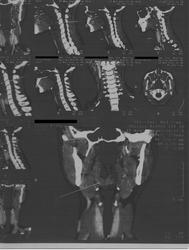

Пациентка 33 года,обратилась с жалобами на чувство инородного тела в гортани,наличие  "кома в горле"в течение 2 х лет.Причину не указывает.Ранее не лесилась.Беременность 5-6 нед. Обследована:эндоскопия ЖКТ без потологии,Лор патологии не выявлено,ФОГ в норме,УЗИ щитовидной железы без патологии. КТ для обсуждения.

2 года "ком в горле", а КТ во время беременности. Даже не забавно... Стрелками указано накопление контраста в язычной миндалине. Скорее гипертрофия+обострение воспаления.

Как гипертрофию язычной миндалины ).Причем ЛОР не видит этой патологии.(В заключении норма).Дама ,к сожалению,согласие не подписывала,и беременность сохранять не будет.Диагноз не установлен.